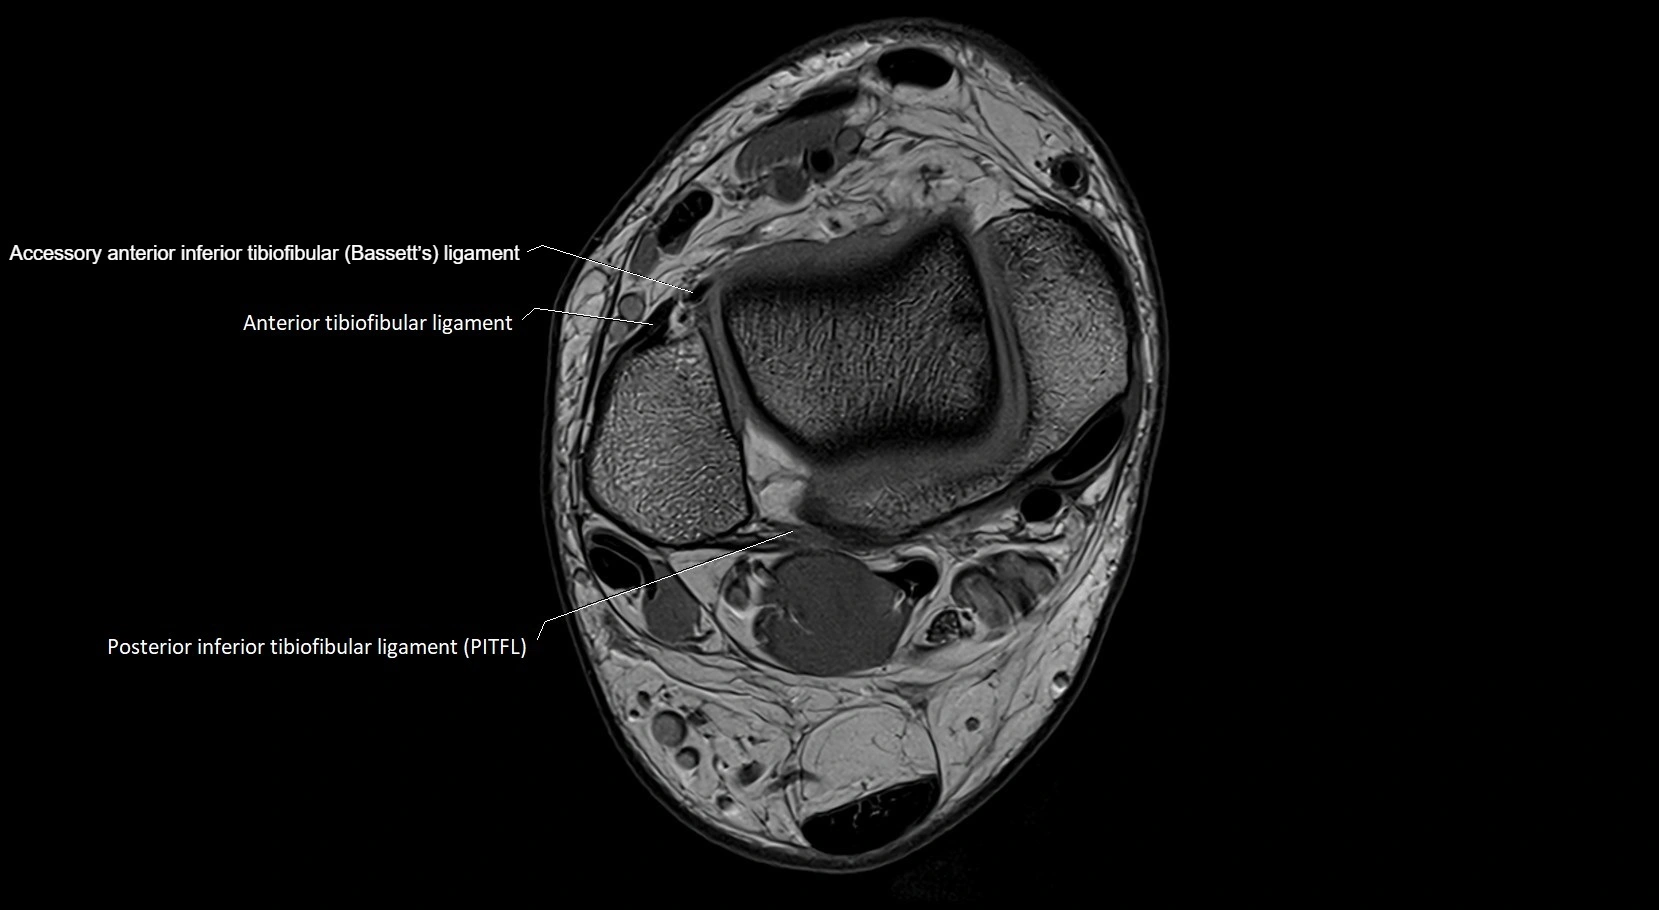

MRI image

image